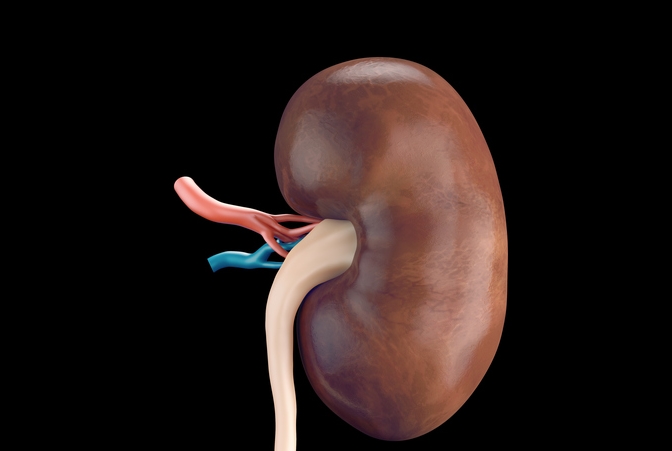

우리가 매일 밥을 먹고, 물을 마시고, 숨 쉬는 그 모든 순간에도 신장은 말없이 일하고 있어요. 마치 조용한 정원사처럼요. 피 속의 노폐물을 걸러주고, 체액의 균형을 맞춰주는 이 신장이 제 역할을 하지 못하면? 그때 우리는 신부전증이라는 이름을 마주하게 됩니다.

신부전증(renal failure)이란 말 그대로 신장의 기능이 정상보다 심하게 저하된 상태를 말해요. 우리 몸에서 꼭 필요한 정화 작용이 제대로 되지 않아, 피 속에 노폐물과 수분, 전해질이 쌓이면서 다양한 이상 증상이 생기죠.

신부전증 진단 방법

신부전증이란 겉으로 보이진 않지만, 검사를 하면 비교적 쉽게 확인할 수 있어요.

- 혈액검사: 크레아티닌 수치, 사구체여과율(GFR)을 확인해요.

- 소변검사: 단백뇨 여부로 신장 손상을 체크할 수 있어요.

- 영상검사: 초음파, CT 등으로 구조 이상을 확인해요.